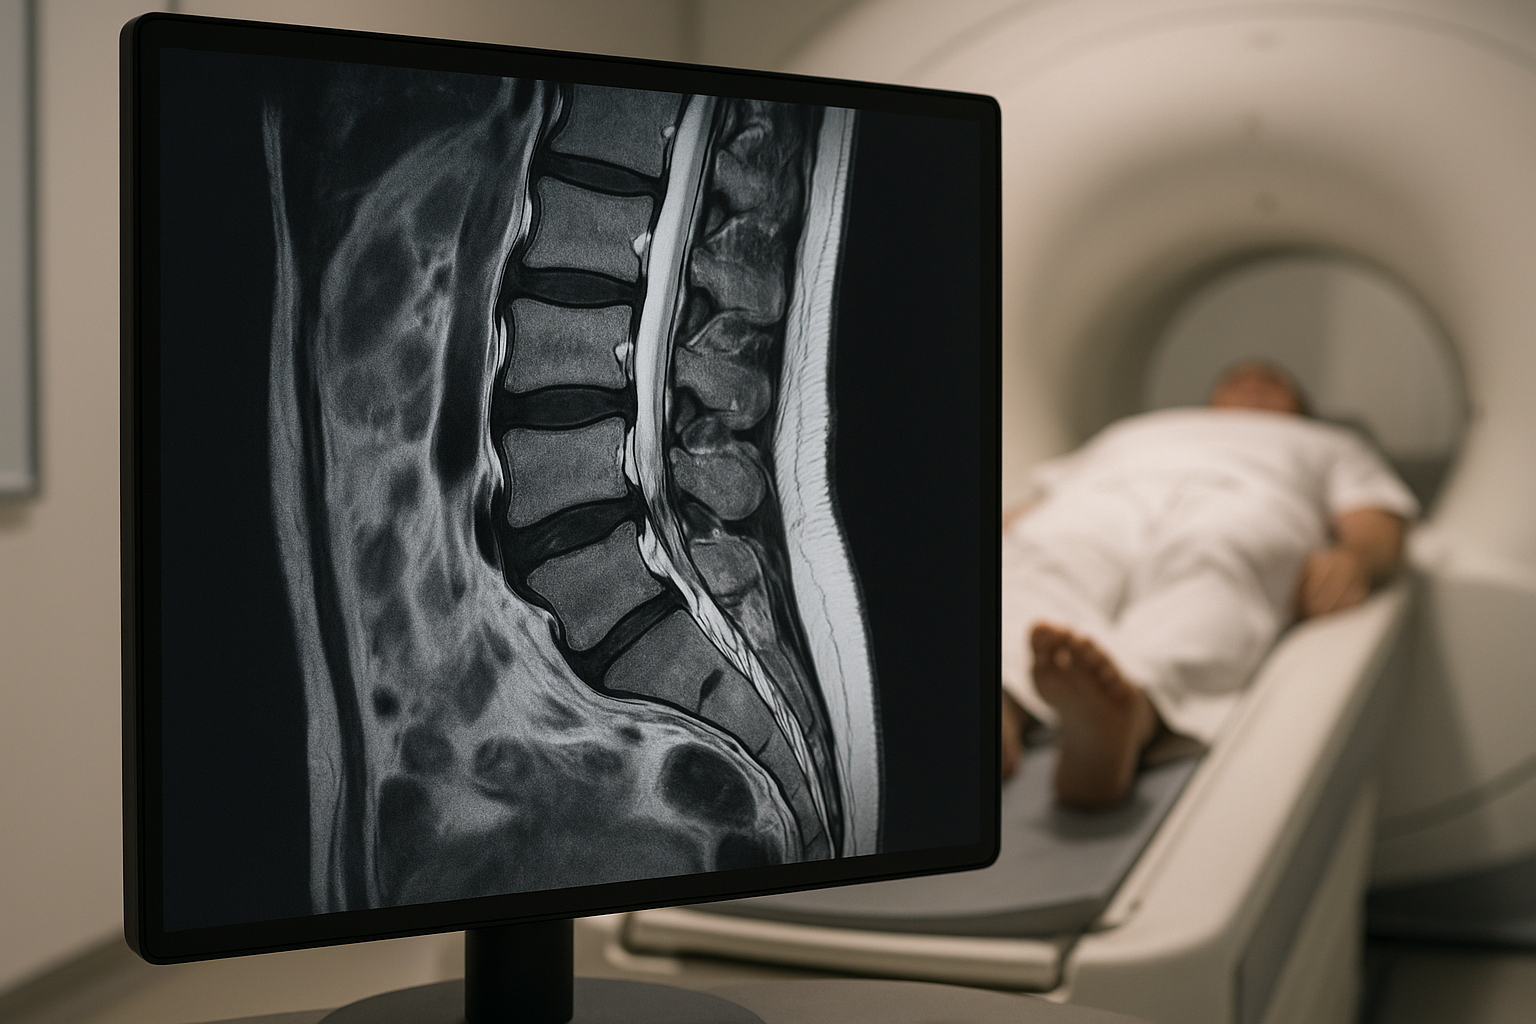

Pregnancy sciatica is primarily caused by the growing uterus and the accompanying weight changes that exert pressure on the sciatic nerve. As the baby develops, the uterus expands, which can lead to nerve compression, especially in the later stages of pregnancy. This compression is often exacerbated by posture changes, as the body adjusts to accommodate the growing baby, leading to increased lumbar lordosis, or inward curvature of the lower spine. Women with a history of back issues may also be more prone to experiencing sciatica during pregnancy.